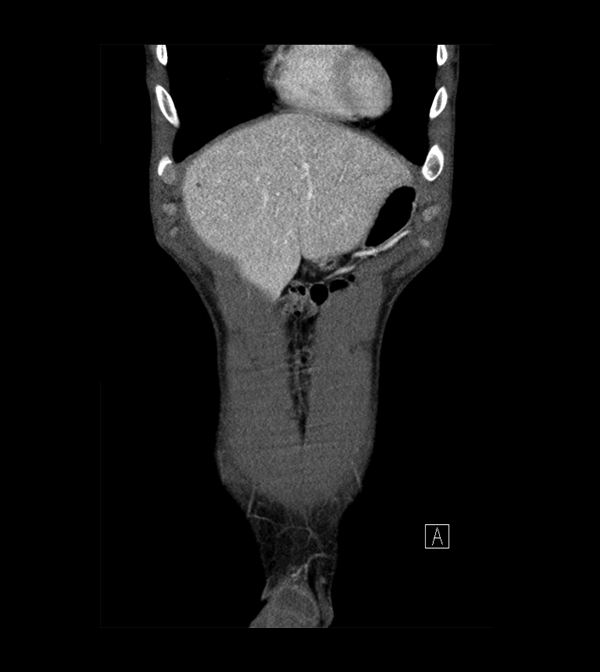

Body

Covers abdominal CT anatomy.